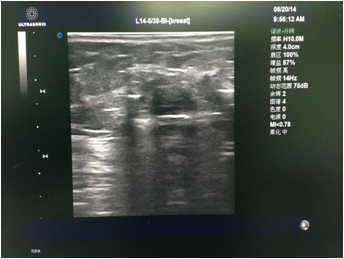

先由主刀医生行彩超检查,和患者确认及核对拟切除的目标病灶。消毒铺巾后医生在彩超引导下于表皮,手术路径及目标病灶周围注射局麻药(图1)。麻醉满意后于彩超引导下进旋切针到目标病灶下方,然后开始切除目标病灶(图2)。最后加压包扎,切除的病灶送病理检查(图3)。整个手术过程于局麻下完成,会有轻微疼痛,但一般程度不重。

图2 图中低回声为肿物,下方白色条索为旋切针。经过旋切后,可以看到肿物消失。